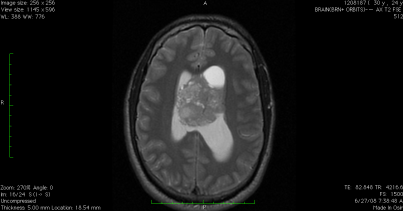

So as part of my new-found quest to be an advocate for brain tumor research and educate the public, I’ve decided to share some of my past MRIs with you.

Let me start with this:

You may recall seeing this MRI in a previous post, but I am sharing it again because this was my very first MRI – the beginning of what I now say defines who I am as a person. The MRI shows the tumor sitting in my ventricular system up against my optic nerve and pushing my brain off to the sides. Hydrocephalus (water on the brain) is also present. Then, there was this from this past March:

Do you see the circle in the lower right-hand corner? If you guessed that is my shunt, then you are correct. It’s amazing what doctors can do today. Because of that device, my brain looks nice and relaxed. There are no obstructions, the hydrocephalus is under control and there is no tumor regrowth.